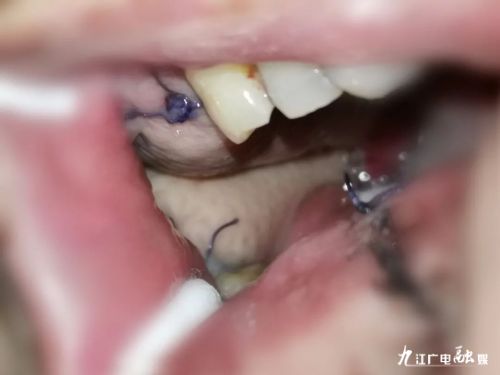

病灶切除

据介绍,患者入院后,便对其进行术前相关检查,结果显示无明显手术禁忌症。因患者既往手术时部分软腭被切除并形成口鼻瘘,造成语言交流困难以及进食不便,对生活影响极大,故患者有强烈的修复意愿。因此,耳鼻咽喉头颈外科团队经过讨论,决定在对其进行“右上颌颊颈联合根治术”的同时,采用“游离股前外侧皮瓣”同期进行术后修复缺损。

本次手术属特大型手术,修复缺损的皮瓣来自患者大腿外侧的皮肤组织,其实就是用大腿的皮去补嘴巴里的缺损。虽然原发病灶切除手术比较常见,但是切除后遗留的组织缺损会给患者后续的生活造成极大不便,目前主流的方法就是用利用各种皮瓣进行修复。而游离皮瓣是其中最为复杂的修复方式,这要求术者除了具有良好的解剖知识外,还需要有稳定的显微外科技术,另外,因为手术时间长(约10小时),对术者的体能还有一定的要求。

因“游离股前外侧皮瓣”适应症宽,应用广泛,又被称为“万能皮瓣”。目前,该皮瓣已成为头颈部组织缺损修复的主力皮瓣。一般用于吻合的血管约2mm粗细,需要在显微镜的辅助下进行。如果皮瓣出现供血不足或回血障碍造成皮瓣危象,就需要及时进行皮瓣的抢救,对手术医生也是极大的挑战。目前,该患者已康复出院。